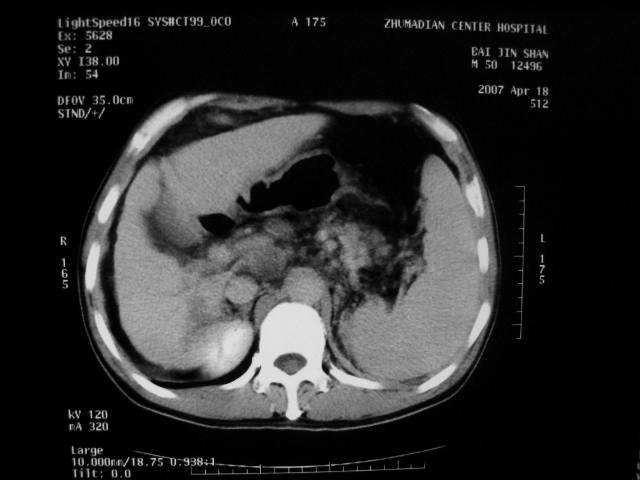

动脉期病灶见轻度强化,考虑肝癌可能性大。

动脉期轻度强化 考虑 肝右叶小肝癌可能性大

1、肝右叶低密度灶考虑肝癌

2、肝硬化

肝硬化、脾大,静脉曲张,肝右叶低密度灶,增强无明显强化,还是考虑肝癌可能性大,建议结合afp检查。

考虑肝硬化,脾大,静脉曲张,肝右叶低密度灶,右肝癌可能性大。